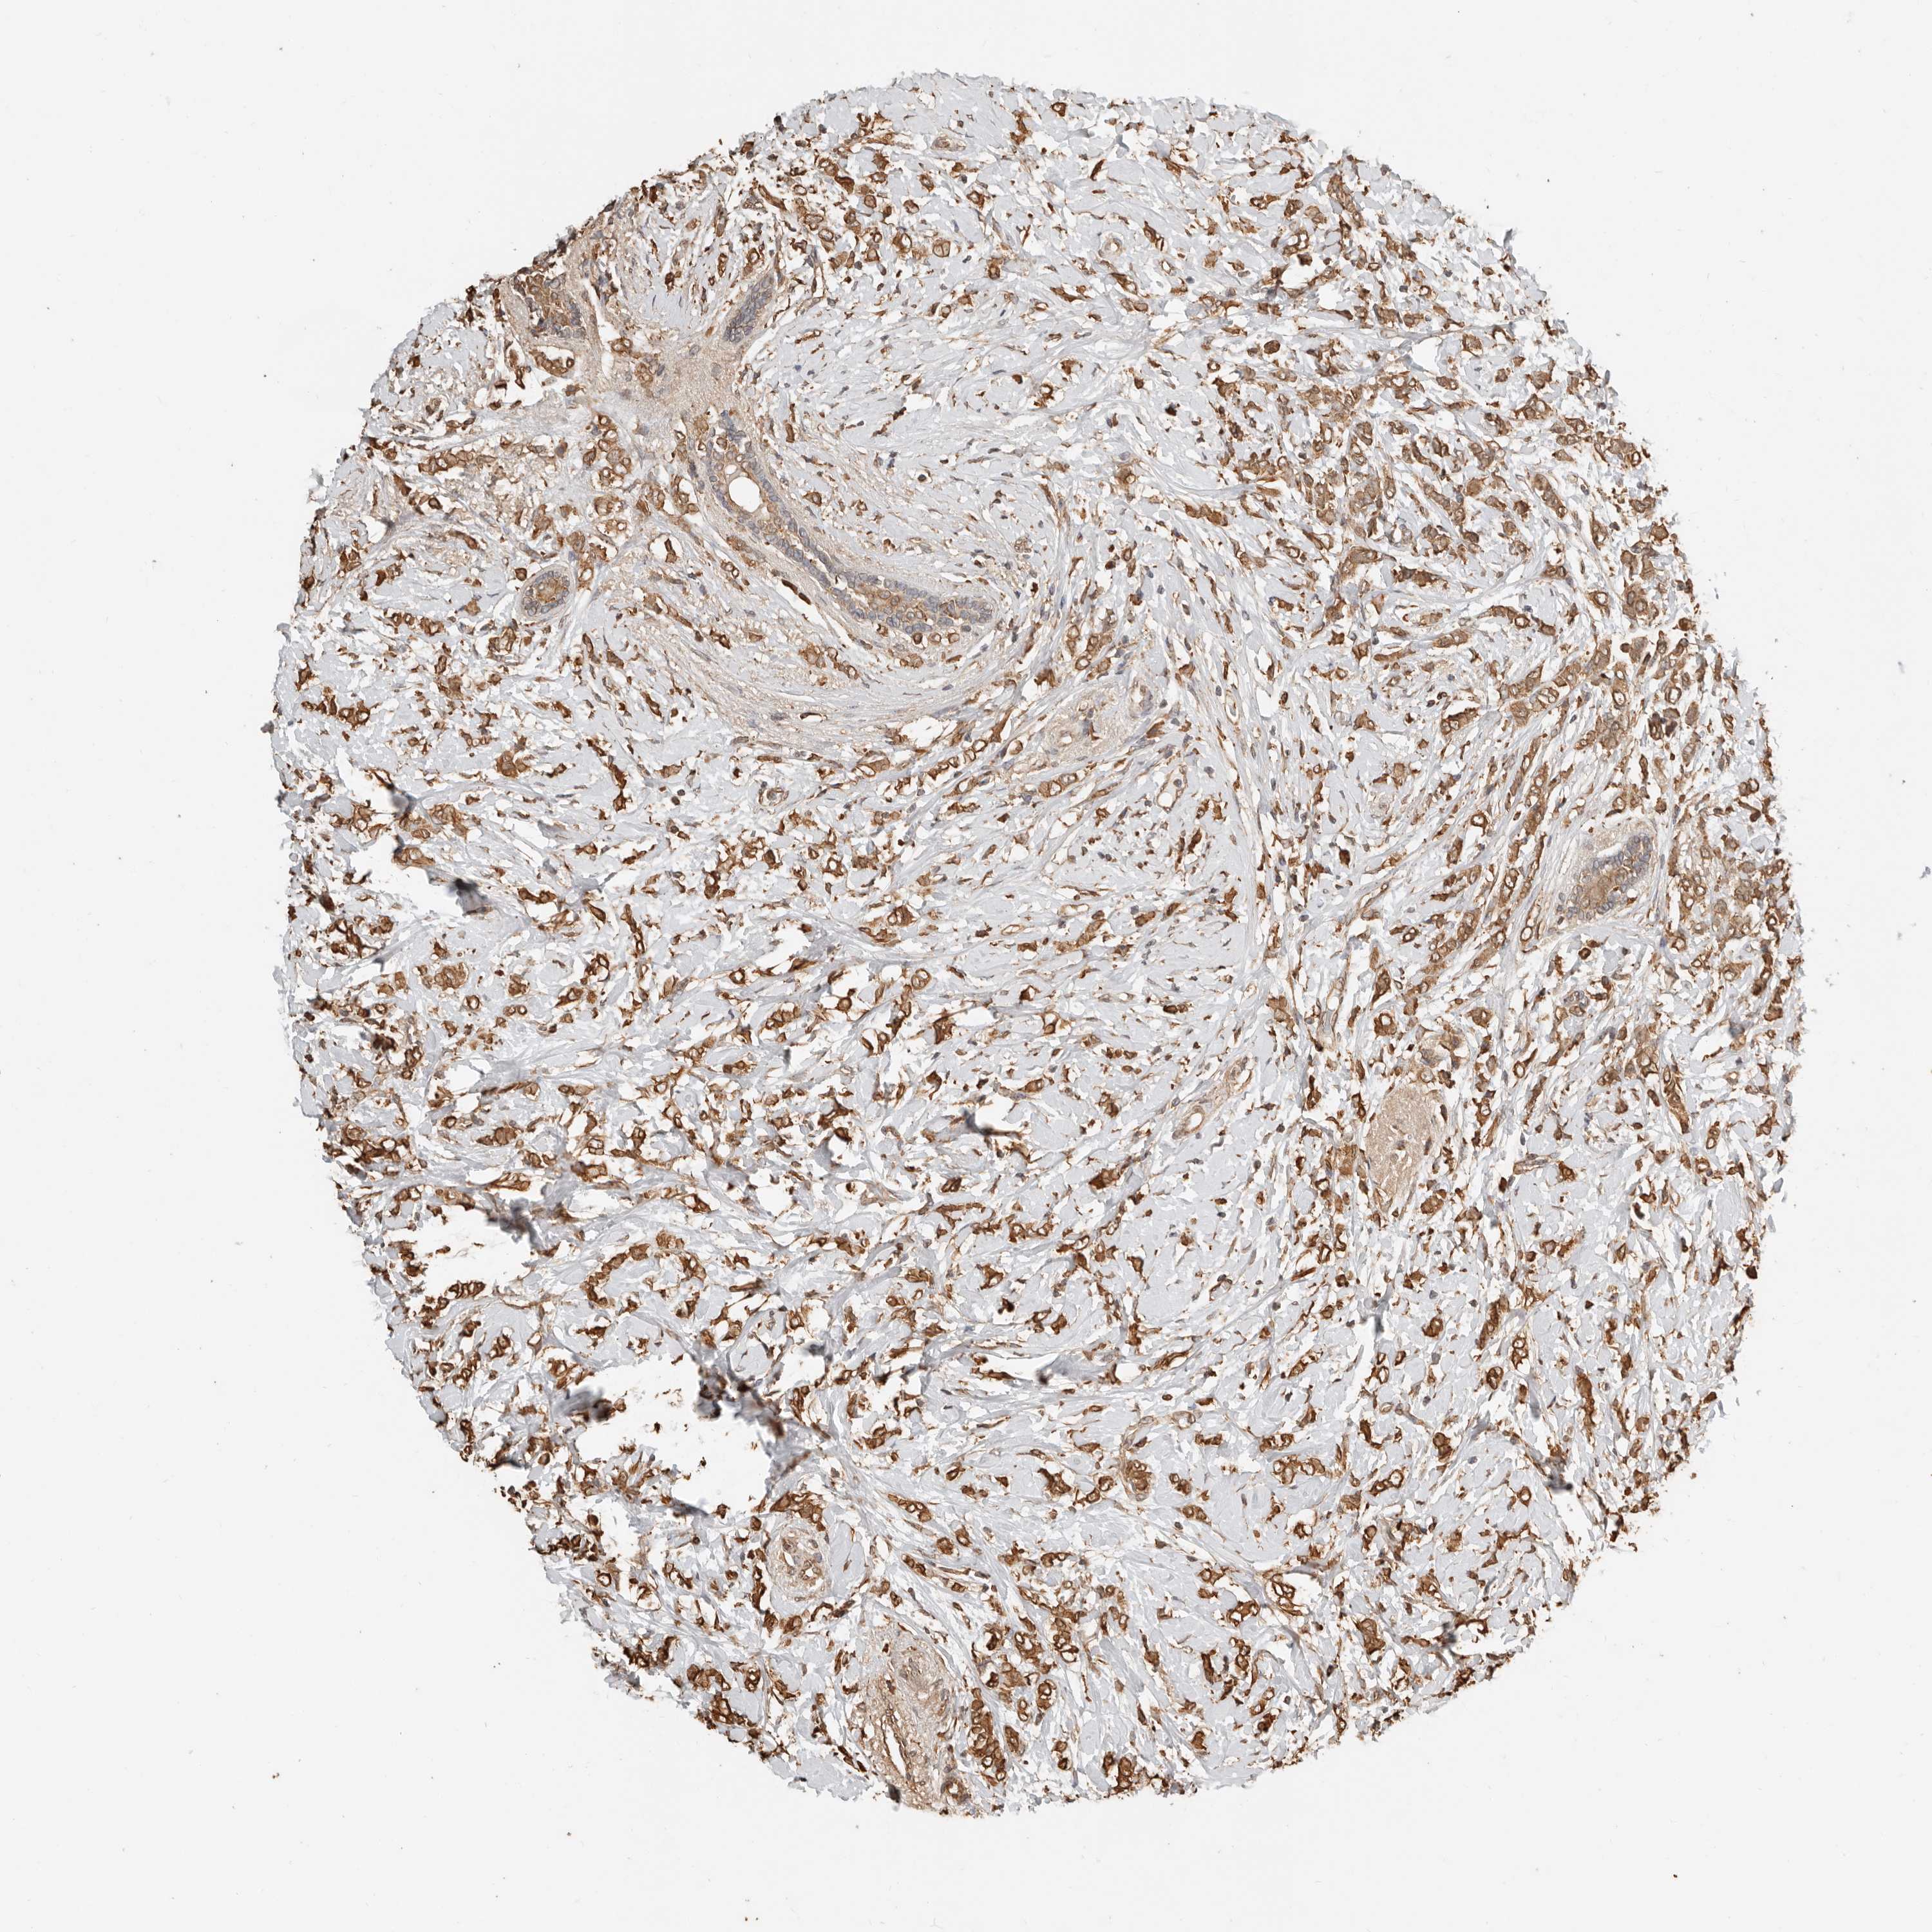

BRCA TCGA BRCA VALIDATION PROTEIN EXPRESSION